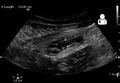

Abdominal ultrasonography, preferably with doppler sonography, is useful to detect appendicitis, especially in children. Ultrasound can show the free fluid collection in the right iliac fossa, along with a visible appendix with increased blood flow when using color Doppler, and noncompressibility of the appendix, as it is essentially walled-off abscess. Other secondary sonographic signs of acute appendicitis include the presence of echogenic mesenteric fat surrounding the appendix and the acoustic shadowing of an appendicolith.[55] In some cases (approximately 5%),[56] ultrasonography of the iliac fossa does not reveal any abnormalities despite the presence of appendicitis. This false-negative finding is especially true of early appendicitis before the appendix has become significantly distended. Also, false-negative findings are more common in adults where larger amounts of fat and bowel gas make visualizing the appendix technically difficult. Despite these limitations, sonographic imaging with experienced hands can often distinguish between appendicitis and other diseases with similar symptoms. Some of these conditions include inflammation of lymph nodes near the appendix or pain originating from other pelvic organs such as the ovaries or Fallopian tubes. Ultrasounds may be either done by the radiology department or by the emergency physician.[57]

Ultrasound showing appendicitis and an appendicolith[58]

Ultrasound of a normal appendix for comparison

A normal appendix without and with compression. Absence of compressibility indicates appendicitis.[55]